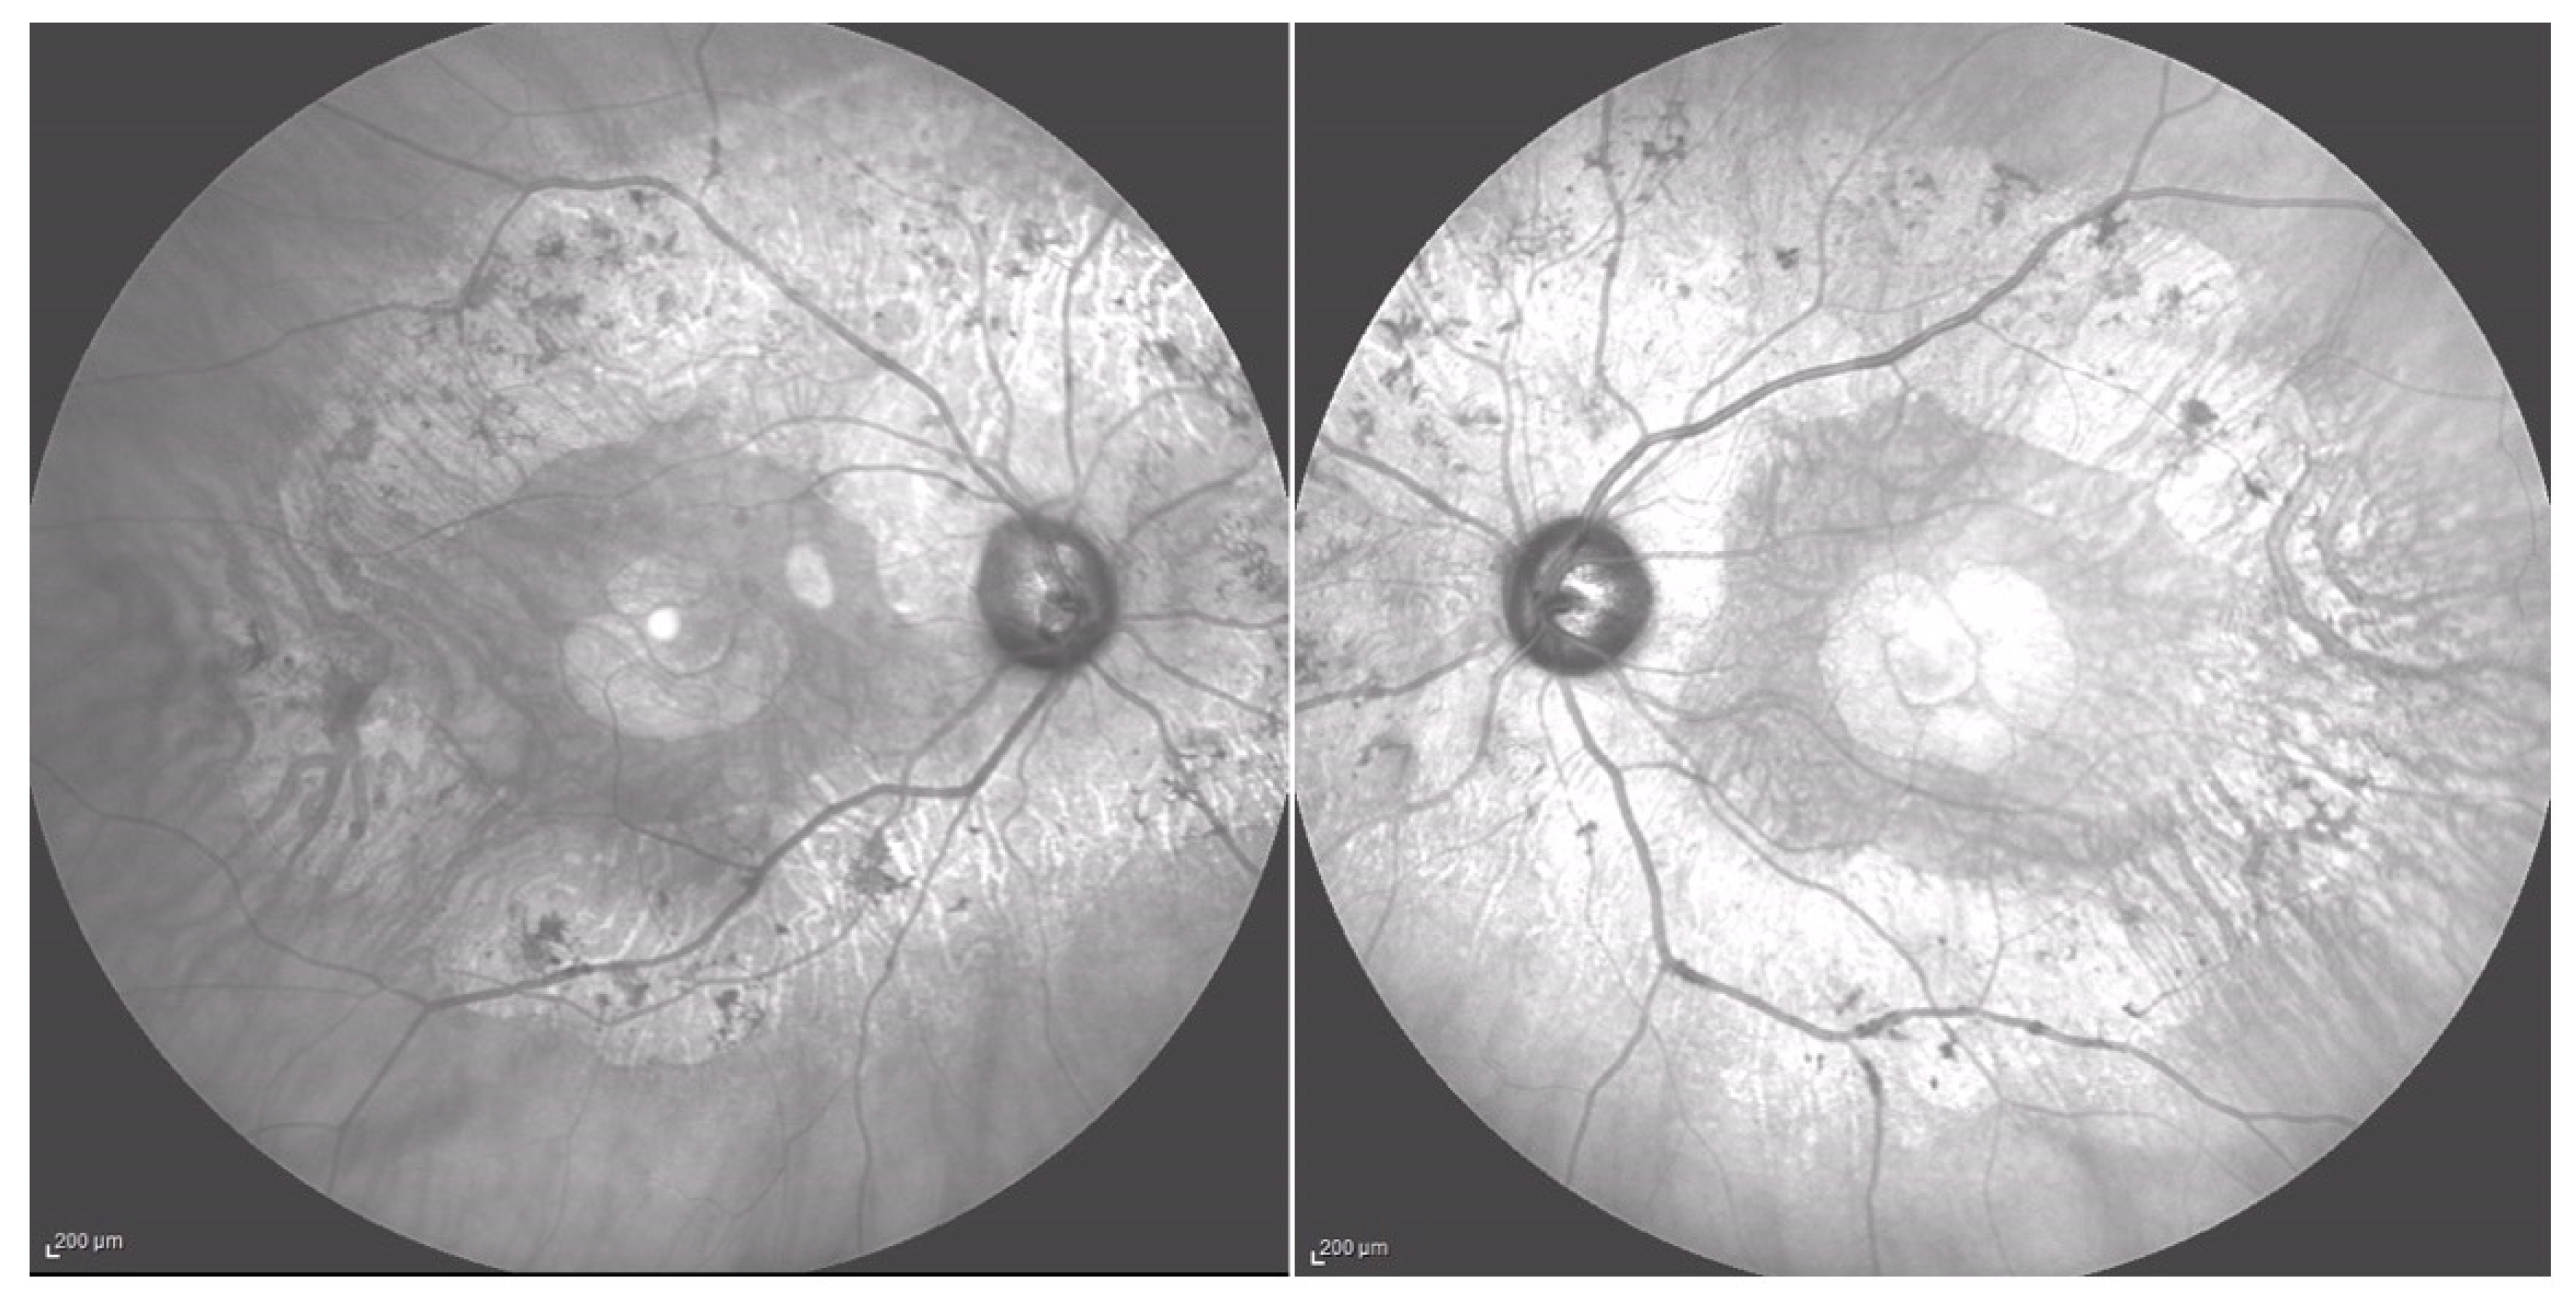

Fundus examination showed vascular attenuation and the presence of typical retinal pigmentary deposits in the form of bone spicules along the nasal and temporal inferior vascular arcades in both eyes (Figure 1). These findings are compatible with a sector RP, even if with a peculiar pericentral distribution of the retina alterations. Additionally, a chorioretinal flat nevus was noted superotemporally in the left eye.

Figure 1. Wide field color fundus retinography (Optomap, Daytona, Nikon) of the right and left eyes of Case 1.